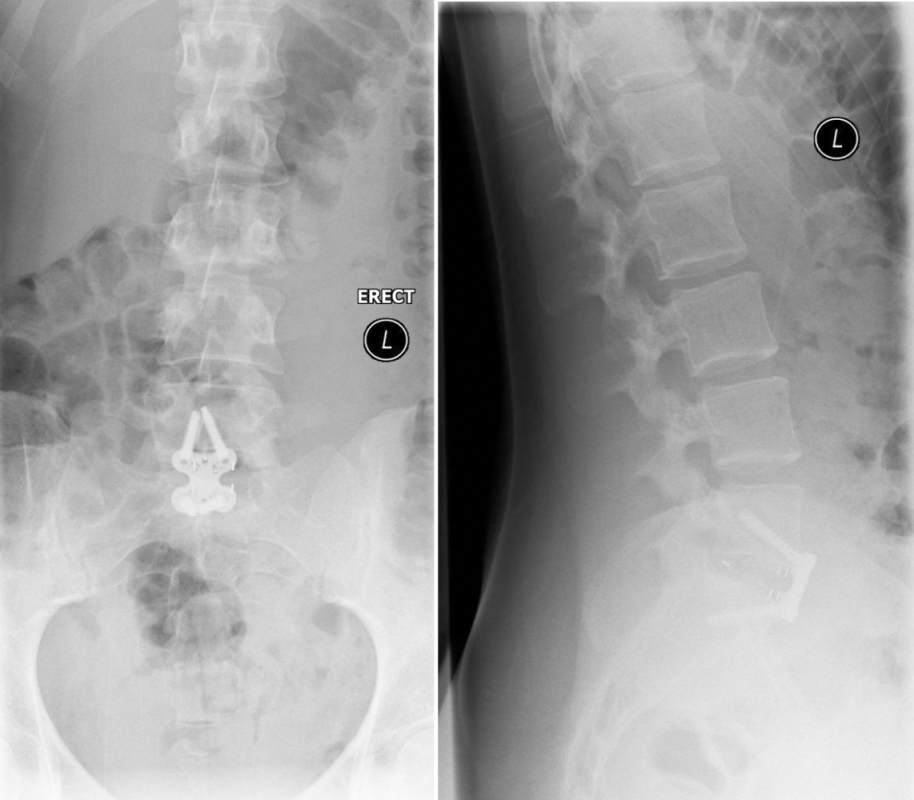

The patient underwent minimal access L5/S1 anterior interbody fusion with BMP followed by minimally invasive Matrix percutanous screw fixation (Fig 11).